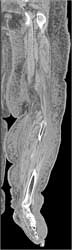

Avascular Necrosis (AVN) Right Hip